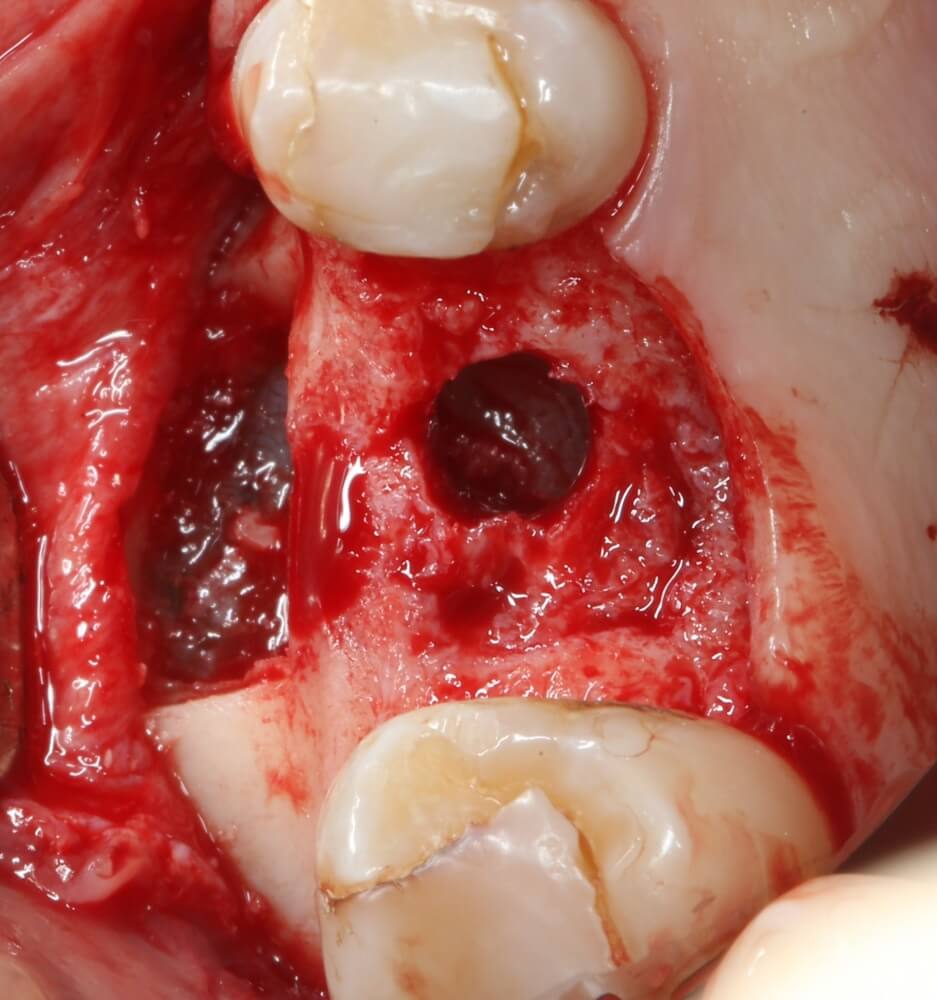

В общем, мы с вами не придурки слесари-столяры, периимплантита не хотим, поэтому кортикальные фрезы не игнорируем:

Кортикальная фреза погружается строго до отметки (см выше). В нашем клиническом случае (с синуслифтингом) это особенно важно, чтобы имплантат не улетел в субантральное пространство. Таким образом получаем лунку, полностью конгруэнтную будущему имплантату. Это очень-очень важно:

Пришло время вернуться к синуслифтингу и заполнить сформированное ранее субантральное пространство графтом (Geistlich Bio-Oss Pen):